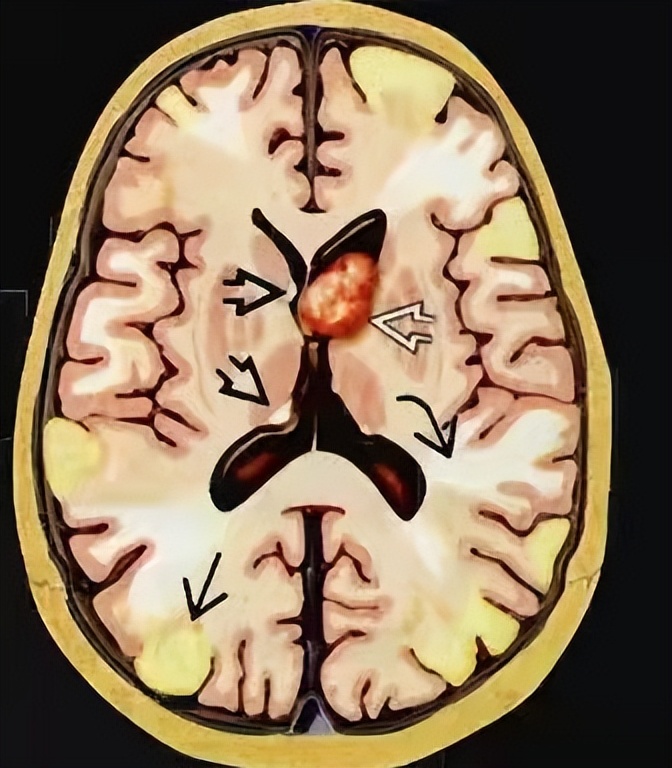

此时杨莹医生心中已经有了初步诊断,但需要影像检查进一步支持诊断,所以她给小王开了头部MRI检查,最终MRI结果显示小王双侧额、顶、颞、枕、岛叶皮层及皮层下多发异常信号,双侧室管膜下多发结节,考虑结节性硬化(见图2)。

图2

当杨莹医生看到MRI报告单,发现支持她最初的诊断,小王具有癫痫+脸上皮脂腺瘤+智力低下临床三联征,同时影像也符合,最后小王被诊断为结节性硬化。

影像上皮质结节及室管膜下结节的发生率为95%(见图3),脑白质异常的发生率为40%-90%。临床治疗主要有mTOR*制剂抑**治疗,是对结节性硬化的病因治疗。抗癫痫药物治疗缓解抽搐。部分可以生酮饮食,可以减少癫痫发作。